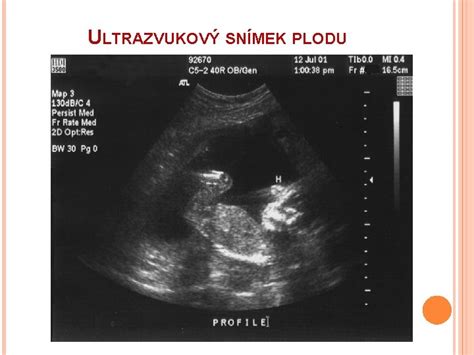

Vývoj dieťatka v maternici je fascinujúci proces. Už v prvých troch mesiacoch sa plod pohybuje, avšak v tomto štádiu je taký malý, že jeho pohyby nie sú cítiť. Jeho presuny a nárazy na stenu maternice sú príliš jemné na to, aby ich matka vnímala. Pohybová aktivita na ultrazvuku je viditeľná, ale nie hmatateľná. Plod sa najprv pohybuje celým telom a s vyvinutím končatín sa jeho pohyby stávajú rozmanitejšími.

Gynekológ MUDr. Vladimír Ferianec zdôrazňuje, že prvorodička môže prvé pohyby cítiť okolo 20. týždňa a neskôr, ale je to veľmi individuálne. „Keď žena cíti pohyby, tak to bude vedieť jasne, že je to ono. Je to niečo, čo dovtedy nezažila a určite bude vedieť, že to nie je napríklad zvýšený pohyb čriev… Okolo 20. týždňa sa robí morfologický ultrazvuk, tzv. II. skríning, ktorý jasne zadefinuje, či daný vývoj plodu aj v prípade, že žena necíti pohyby, je správny.“